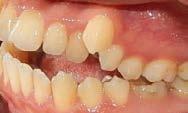

De frente (Figura 7) presenta líneas medias dentales no coincidentes, 6 mm overjet, 10% overbite, relación molar y canina clase II bilateral. Las oclusales (Figura 8) la arcada superior de forma triangular, presencia de OD 53 y apiñamiento severo, la arcada inferior de forma cuadrada con segundos molares en erupción y apiñamiento moderado.

Figura 5. Corte coronal. Figura 6. Corte sagital. Figura 7. Intraorales de frente, lateral derecha e izquierda. Figura 8. Vista oclusal superior e inferior.